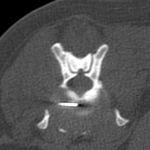

10歳のラブラドールがうまく起立できないとのことで来院されました。神経学的な検査からL7〜S1における腰仙椎間におけるHansen TypeⅡの椎間板ヘルニア、馬尾症候群が疑われました。MRIを撮像したところ、L1~L2にも椎間板ヘルニアが確認されたことから、L7〜S1の椎間板ヘルニアと2ヶ所、同時にPLDDで経皮的に除圧術を行うことになりました。大きな切開を必要としないため翌日退院となります。しばらくは安静にしつつ徐々にリハビリを開始します。